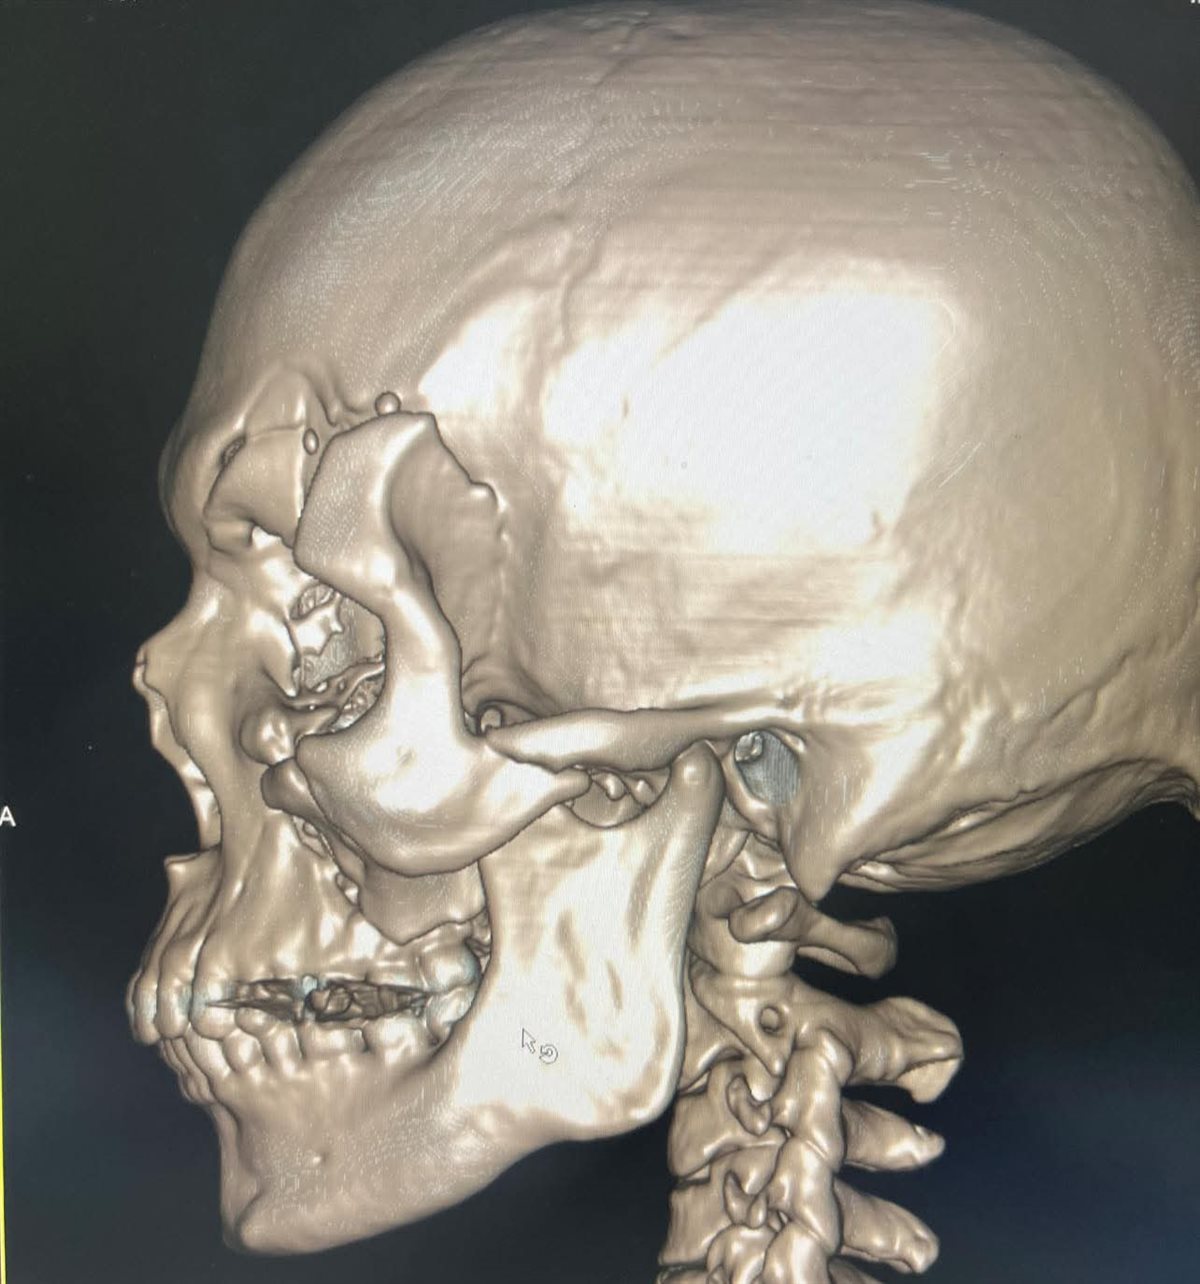

وكان المريض قد وصل إلى المستشفى بعد مرور 40 يومًا على الحادث، حيث كان قد مكث بإحدى المستشفيات دون تدخل جراحي نظرًا لصعوبة الحالة، ما أدى إلى بدء التحام العظام بشكل غير صحيح، وزيادة تعقيد التدخل الجراحي.

وخلال عملية استمرت نحو 9 ساعات متواصلة، تم تنفيذ تدخل جراحي متكامل شمل استخدام مدخل جراحي تجميلي (Bicoronal Approach) لإتاحة رؤية جراحية واسعة مع الحفاظ على الشكل الجمالي، إلى جانب التعامل مع قاعدة الجمجمة وإجراء Cranization للجيب الجبهي، بما يضمن حماية المخ.

كما تم إعادة بناء محجر العين والجيب الأنفي باستخدام عظام ذاتية من المريض (Autogenous Bone Graft) مع تدعيمها بشبكة تيتانيوم، إلى جانب إعادة تثبيت عظام الوجه والجمجمة باستخدام الشرائح والمسامير لاستعادة التماثل التشريحي الكامل.